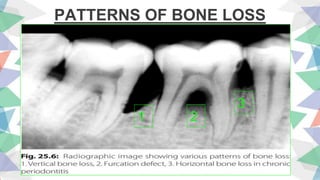

PATTERNS OF BONE LOSS

1. When attachment and

bone loss on one tooth

surface is greater than

that on adjacent

surface.

2. Associated with angular

bony defects and

infrabony pocket

formation.

bone loss proceeds at

uniform rate on the

majority of tooth

surfaces.

2. Associated with

suprabony pockets.

VERTICAL HORIZONTAL

1 2

3